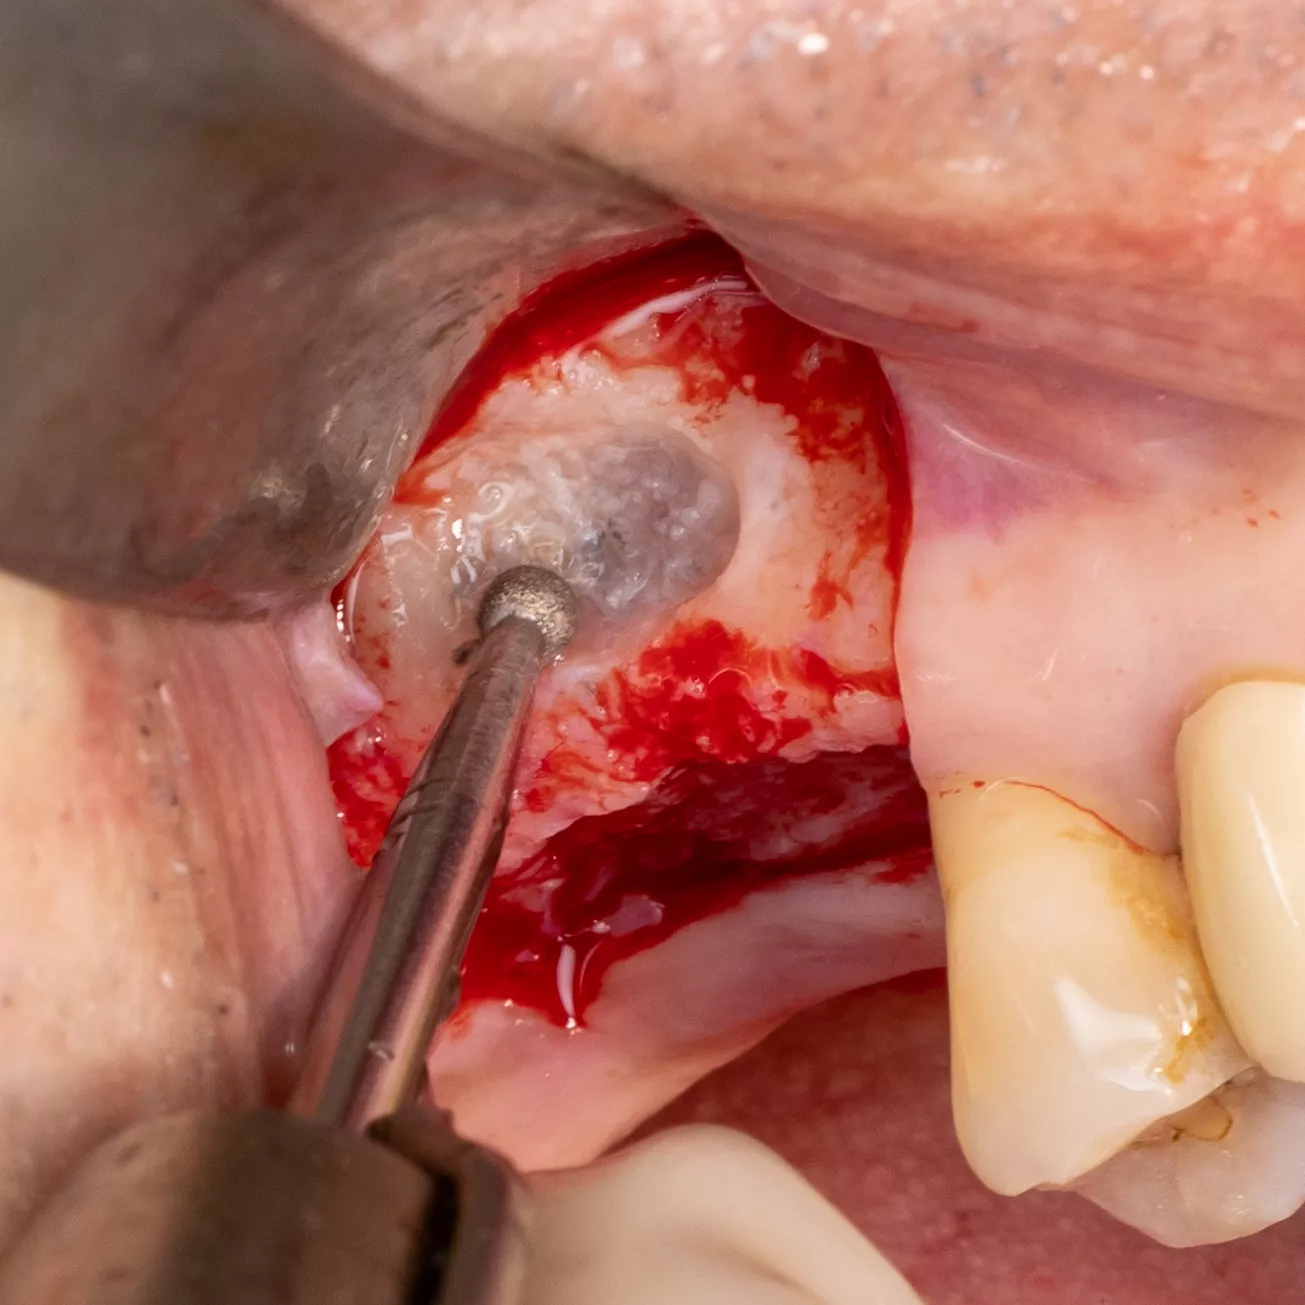

4. Sinus window : Subtractive osteotomy without preservation of the bone flap using a 2.5 mm diamond bur mounted on a surgical handpiece. The Schneiderian membrane (sinus mucosa) of slightly bluish grey color is exposed.

5. Initiation of lifting of the sinus mucosa through the inferior mesial window angle.